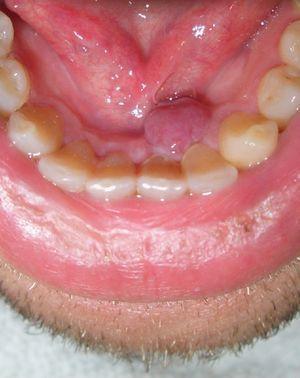

Exploración físicaEn la exploración se apreciaba un nódulo exofítico, sésil, de aspecto carnoso, de 8mm de diámetro y de superficie lisa, localizado en la región interior de la encía inferior (fig. 1). En la valoración general del paciente no se palpaban adenopatías locorregionales ni se detectaron otras lesiones cutáneo-mucosas asociadas.